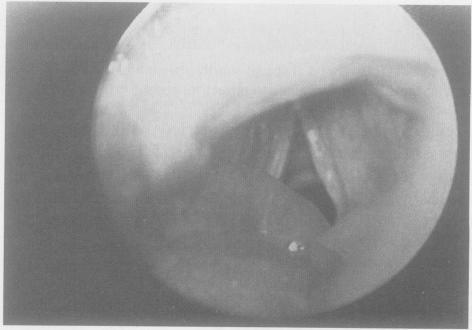

Severe angioedema and respiratory distress associated with lisinopril use.

West J Med. 1993 Apr;158(4):412-7.

PMID:8391190

原文链接:https://pmc.ncbi.nlm.nih.gov/articles/PMC1022079/